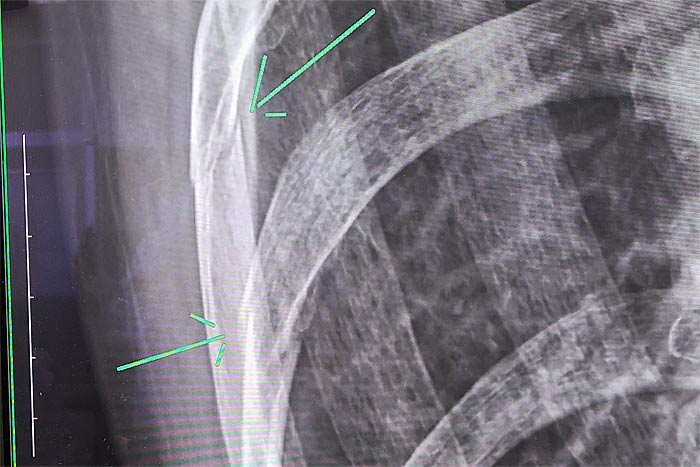

そうして診察の結果、肋骨2本が折れ、1本にヒビが入っていることが判明。

予想より重症だったけれど、肺の機能に影響はなく、このまま旅を続けても問題ないだろうと先生が言ってくれた。

診断結果

私が「旅の記念にレントゲンの写真を撮りたい」と言うと、分かりやすいように矢印を書き込んでくれた。